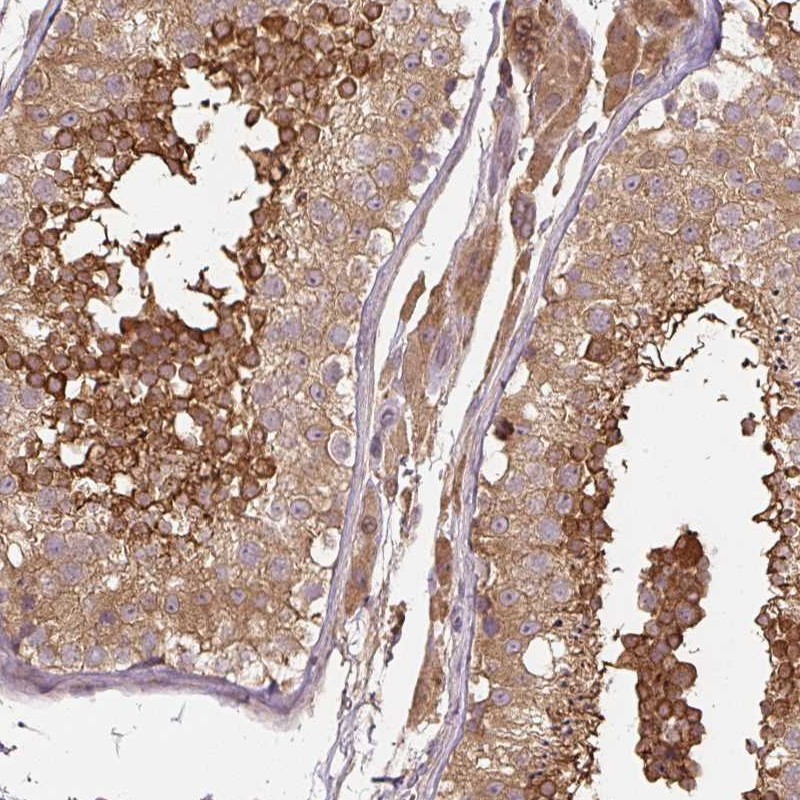

Immunohistochemical staining of human testis shows strong cytoplasmic positivity in cells in seminiferus ducts.